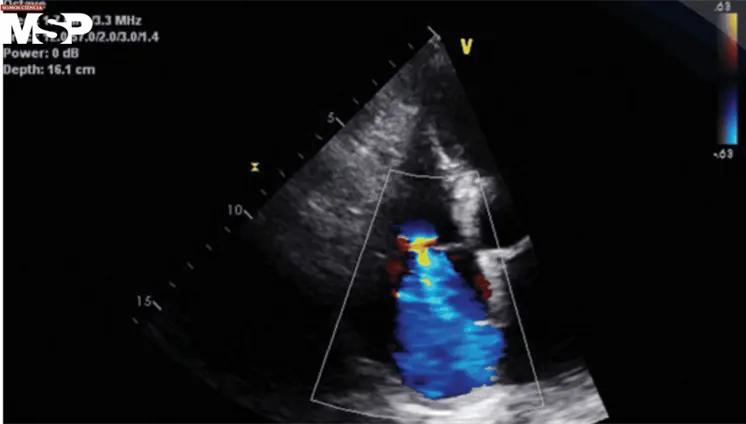

La trombosis de la vena espermática está asociada a enfermedades inflamatorias intestinales, como la colitis ulcerativa y la ileítis terminal, que generan un estado protrombótico debido a su naturaleza inflamatoria.